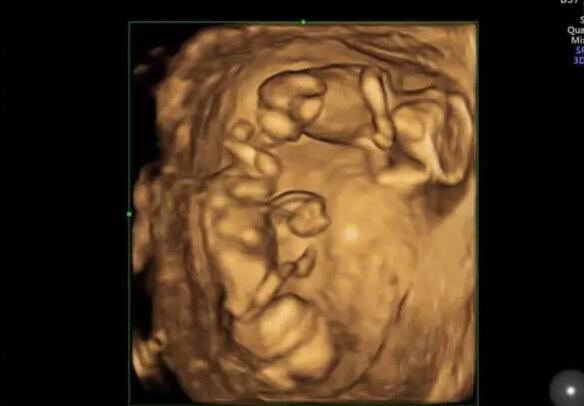

山东试管供卵 山东生殖医院三代试管多少钱 ‘四维女孩三条线图片’